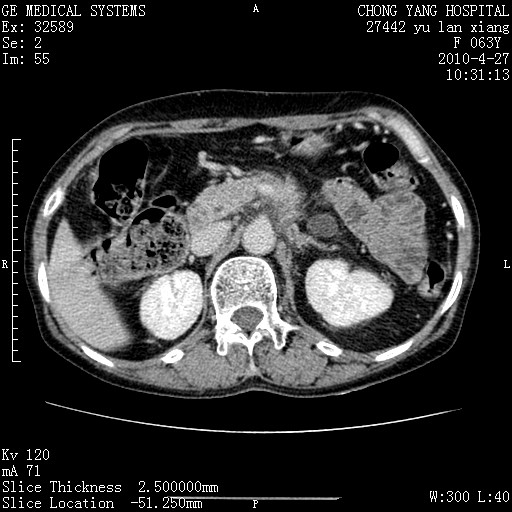

标题: CT26066:F63Y 上腹正中压痛半月,CA199:7400u/ml,MR示胰腺炎伴 [打印本页]

胰腺癌侵犯腹腔动脉干-分支、胃壁、左侧膈肌伴胰周及腹膜后淋巴结转移、胆囊切除术后。

胰腺癌侵犯腹腔动脉干-分支、胃壁、左侧膈肌伴胰周及腹膜后淋巴结转移、胆囊未显影。